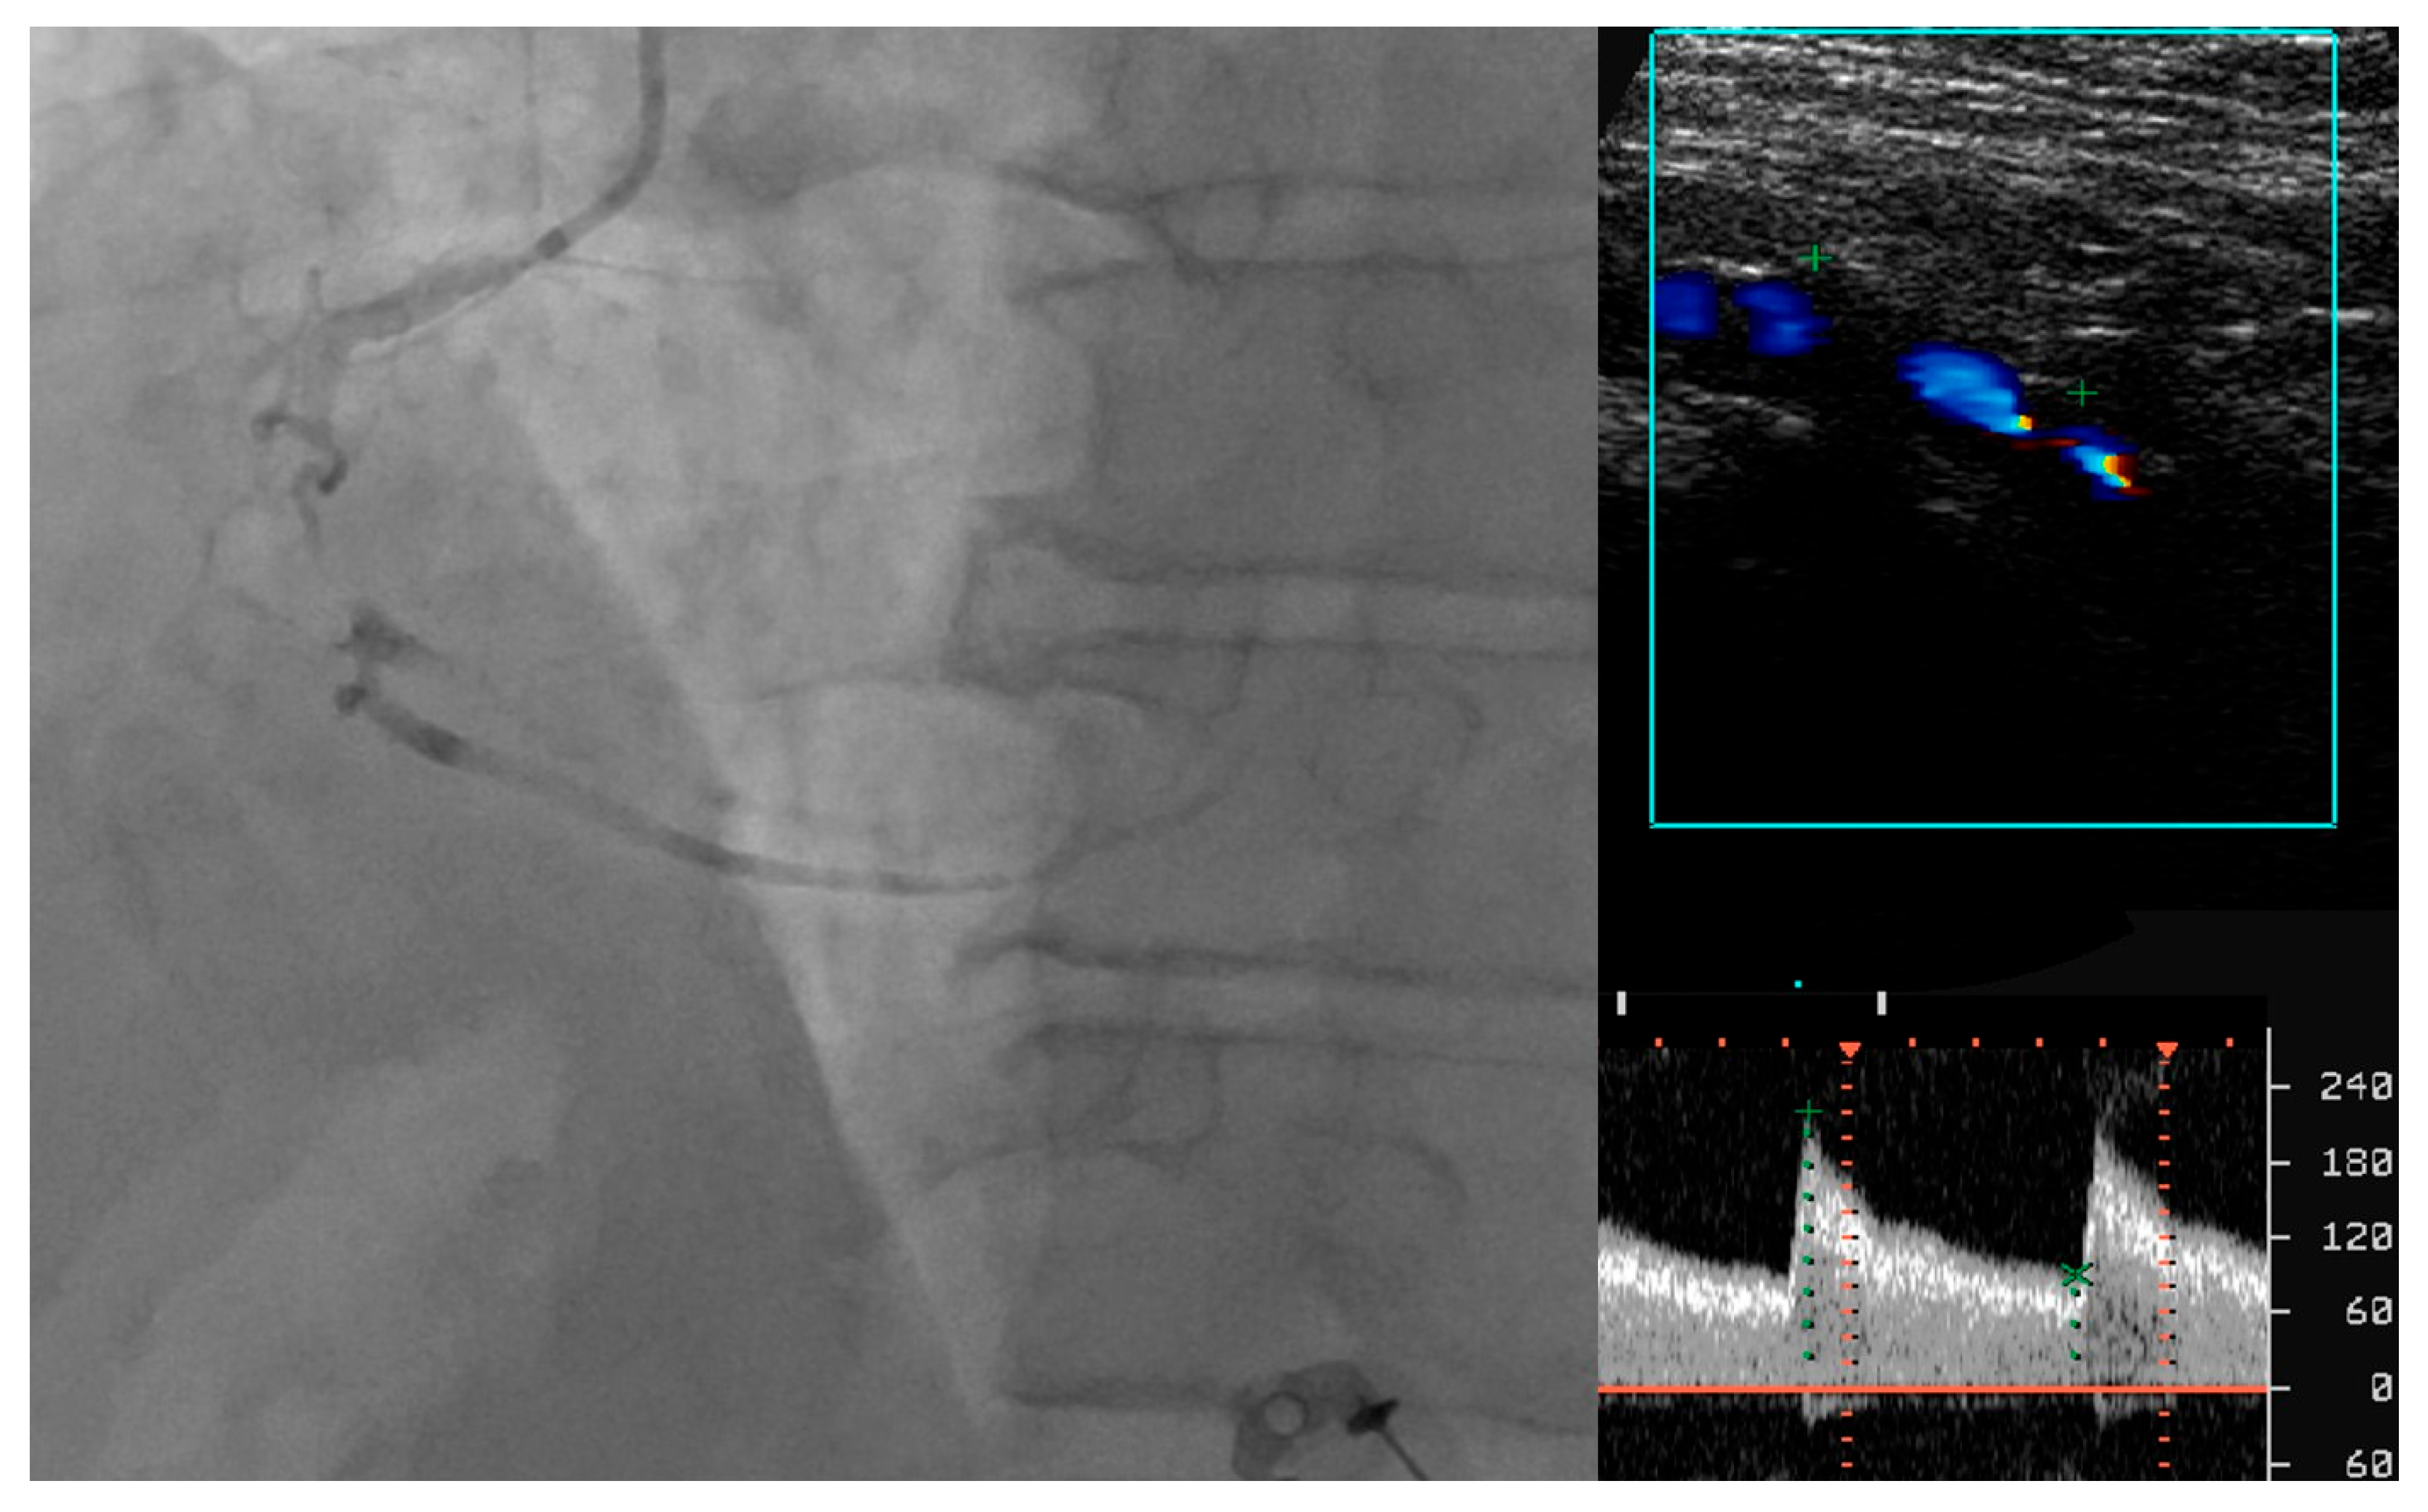

- Tătaru, D.A.; Olinic, M.; Homorodean, C.; Ober, M.C.; Spînu, M.; Lazăr, F.L.; Onea, L.; Olinic, D.M. Correlation between Ultrasound Peak Systolic Velocity and Angiography for Grading Internal Carotid Artery Stenosis. J. Clin. Med. 2024, 13, 517. [Google Scholar] [CrossRef] [PubMed]

- Quisi, A.; Kurt, I.H.; Şahin, D.Y.; Kaypaklı, O.; Söker, G.; Kaya, Ö.; Allahverdiyev, S.; Genç, Ö.; Alıcı, G.; Koç, M. Evaluation of the relationship between renal resistive index and extent and complexity of coronary artery disease in patients with acute coronary syndrome. Kardiol. Pol. 2017, 75, 1199–1207. [Google Scholar] [CrossRef]

- Geraci, G.; Buccheri, D.; Zanoli, L.; Fatuzzo, P.; Di Natale, K.; Zammuto, M.M.; Nardi, E.; Geraci, C.; Mancia, E.; Zambelli, G.; et al. Renal haemodynamics and coronary atherosclerotic burden are associated in patients with hypertension and mild coronary artery disease. Exp. Ther. Med. 2019, 17, 3255–3263. [Google Scholar] [CrossRef] [PubMed]